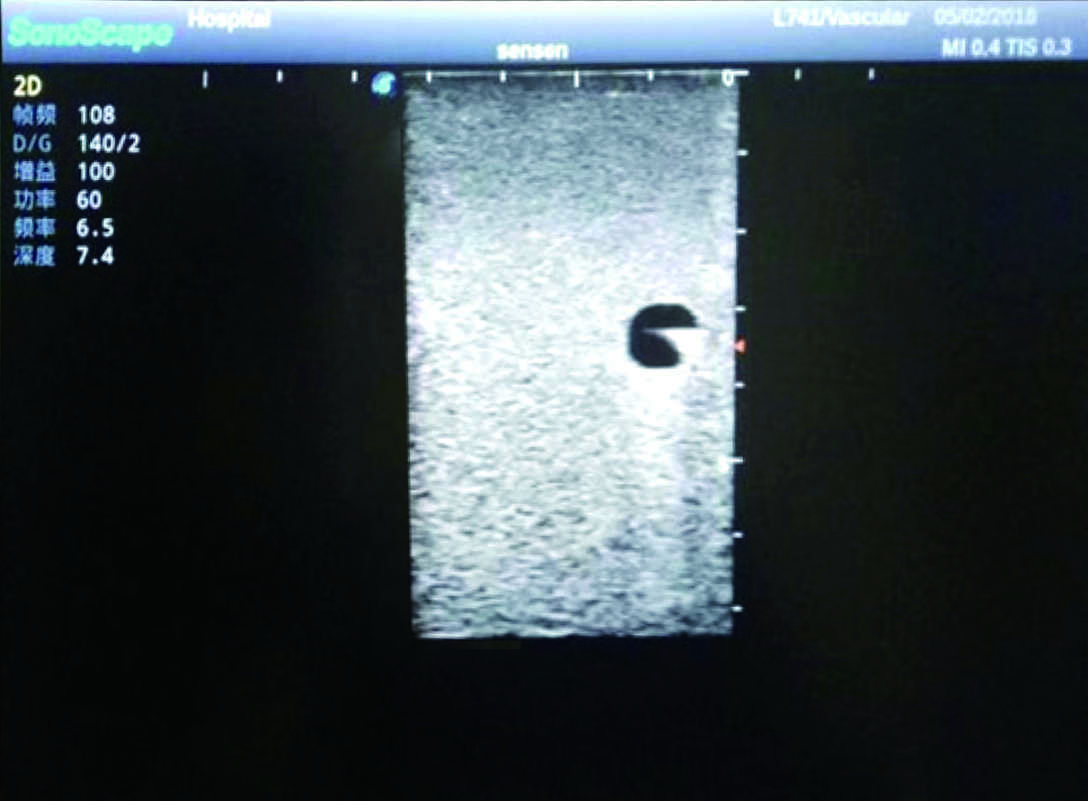

Model TYE1510.1

Product size(mm) 700×500×160

It is a model covering up from lobulus auriculae plane to the umbilical plane, and it has anatomical structures like clavicle, rib, sternocleidomastoid, jugular vein and basilic vein.

1)   Made of high molecular polymer ultrasound material, close to the real skin

2)   It can be used by real ultrasound machines

3)   Clear and real images of the tissues and organs (basilic vein and superior vena cava)